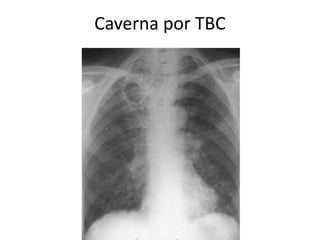

Caverna por TBC

3. PATRÓN DESTRUCTIVO

1. Cavidades de pared gruesa: abscesos